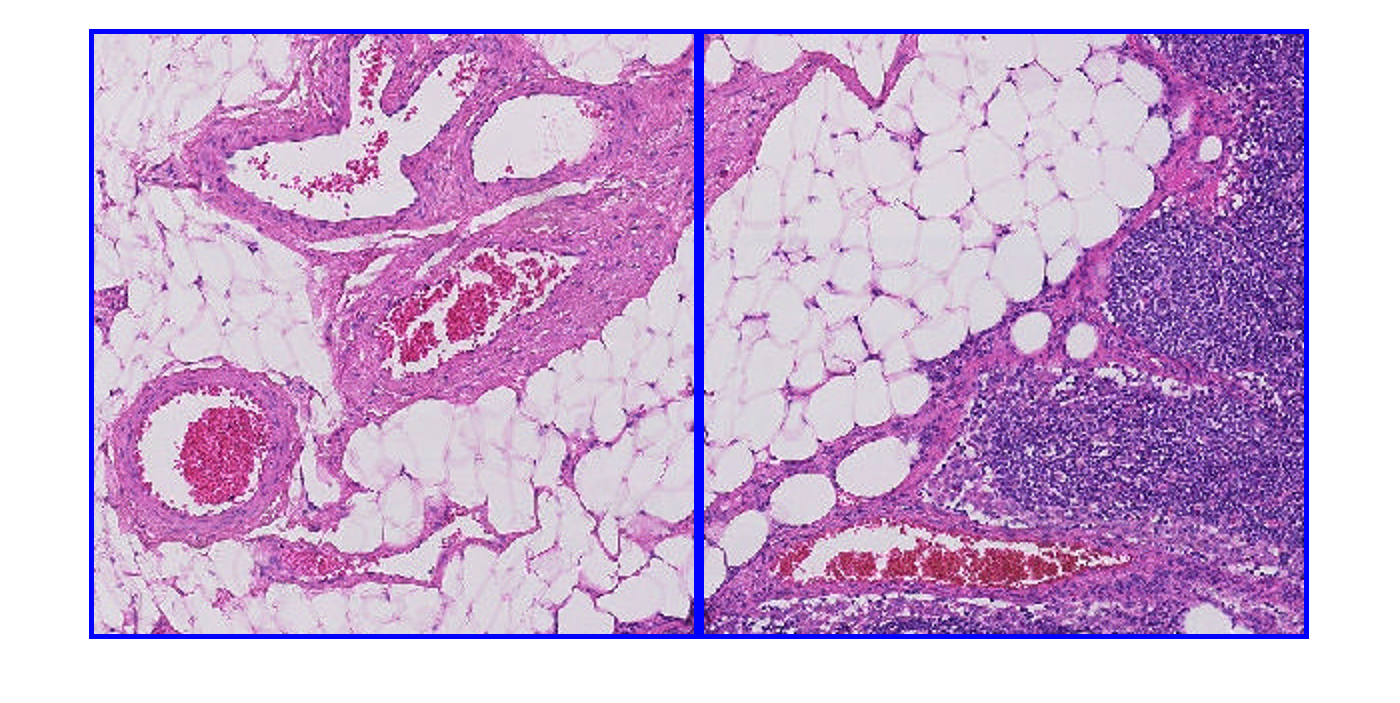

Создайте bigimage. Это примеры использует модифицированную версию изображения "tumor_091.tif" от набора данных CAMELYON16. Оригинальное изображение является учебным изображением лимфатического узла, содержащего ткань опухоли. Оригинальное изображение имеет восемь уровней разрешения, и самый прекрасный уровень имеет разрешение 53760 61440. Модифицированное изображение имеет только три крупных уровня разрешения. Пространственная ссылка модифицированного изображения была настроена, чтобы осуществить сопоставимое соотношение сторон и указать функции на каждом уровне.

Загрузите bigimage. Это примеры использует модифицированную версию изображения "tumor_091.tif" от набора данных CAMELYON16. Оригинальное изображение является учебным изображением лимфатического узла, содержащего ткань опухоли. Оригинальное изображение имеет восемь уровней разрешения, и самый прекрасный уровень имеет разрешение 53760 61440. Модифицированное изображение имеет только три крупных уровня разрешения. Пространственная ссылка модифицированного изображения была настроена, чтобы осуществить сопоставимое соотношение сторон и указать функции на каждом уровне.